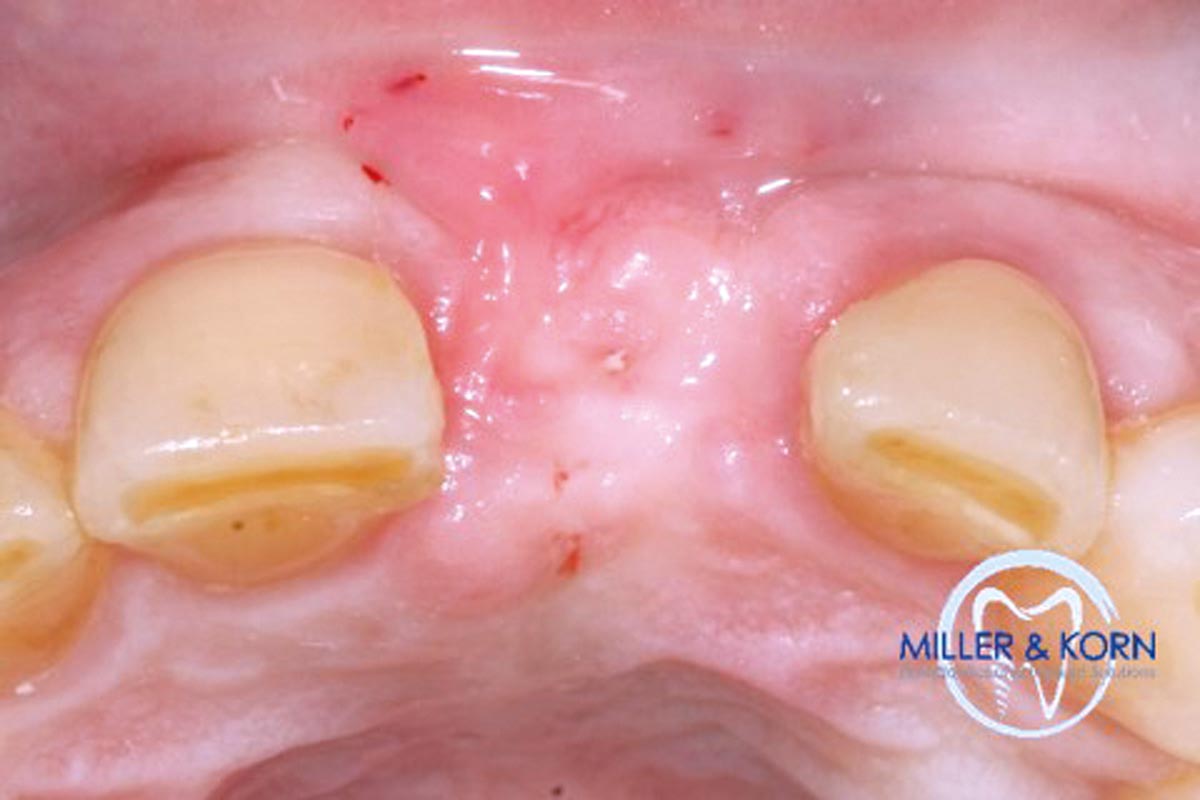

60-year-old female patient presented with a chronic infection on tooth #11.

Since she has a high lip line matching the gingival margins of the adjacent central incisor and creating a root eminence is extremely important. For these reasons, the treatment of choice was an allograft bone ring enabling immediate placement of the dental implant with simultaneous regeneration of her ridge.

The patient presented with pathologic mobility of upper left central incisor. Radiographic examination revealed significant circumferential attachment loss with an unfavorable crown to root ratio.